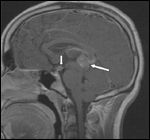

FIGURE 4

Medulloblastoma

• Medulloblastoma-Medulloblastoma is the most common malignant brain tumor in children. About 400 children are diagnosed with this tumor each year in the United States.[1] The peak age of onset is between 5 and 9 years. Over 90% of medulloblastomas typically arise from the superior medullary velum, growing to fill the cavity of the fourth ventricle (Figure 4).[33] The tumor mass can encroach on to the cisterna magna and sometimes infiltrates the floor of the fourth ventricle or brain stem. A minority of tumors, particularly in patients over 16 years of age, arise more laterally in the cerebellar hemispheres.[33] Macroscopically, these tumors are soft, friable, and moderately demarcated from the cerebellar tissue. Areas of central necrosis may be present.